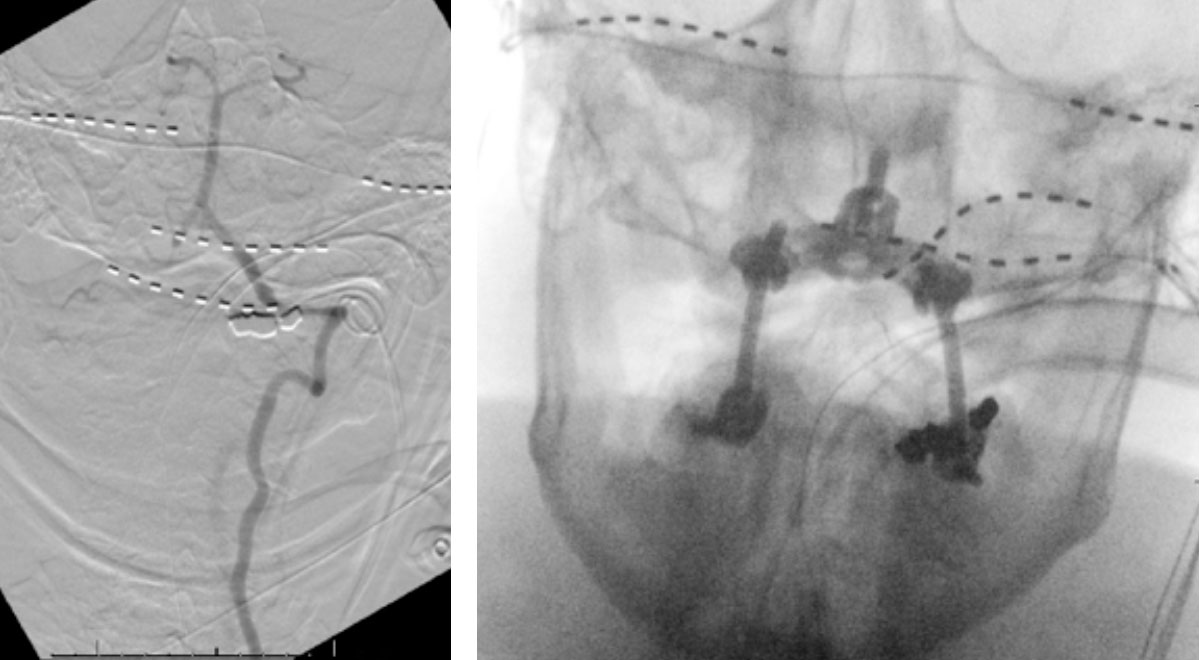

The patient was brought to the operating room, and general tracheal anesthesia was initiated via fiberoptic approach. Somatosensory potentials, motor evoked potentials, and brainstem auditory evoked responses were recorded. The patient then underwent intraoperative angiography of the right Vertebral Artery performed via a 5 French Right Radial Artery access. Once it was established that he had good flow, a Mayfield head holder was attached to the patient’s head on the 60 pounds of torque pressure. The Wilson frame attached to the Jackson table was then placed on top the patient attached to the Jackson frame. The patient was secured with straps and bed sheets and then positioned prone by rotating the frame around its axis. The flat plate of the Jackson table was then removed, and the patient bony prominences and soft tissues were adequately padded. Angiography was then again repeated showing good flow through the Vertebral Artery. After that, after being properly secured to the table with access to the right radial sheath, the neck and the left posterior iliac crest area and a tricortical autograft was then obtained with osteotomes. Iliac crest was reconstructed with fiber graft allograft. Posterior cervical incision was then performed and the spinous processes of C2 and C3 were identified and cleared of the fascia and then the muscle the way to the lateral edges of lateral masses. The C1 posterior ring was completely subluxed under the occiput and C2 lamina. The patient evoked potentials remained stable. The C1 lamina was then cleared of the soft tissue laterally on both sides. On the left side, significant osteophyte formation was visualized, and the C1-2 foramen was completely closed by the bone. On the right side, the C1-2 foramen was dissected, and the veins were coagulated with bipolar cautery. The C2 nerve root was identified and then coagulated bipolar cautery and divided with micro scissors, completing the planned C2 rhizotomy. The decision was made to perform an occiput to C3 fusion, since the articulation between the occiput, C1, and C2 was technically difficult and most likely would result in an inadequate fixation. At that point, a small occipital plate was brought into the field, and secured to the suboccipital bone with 14- and 12-mm screws. Then a pilot hold was created into the lateral masses of C3 bilaterally. The C3 appeared to be solidly fused to C2. First a hole was made with the drill and then passes were made with 40 mm drill with the guide. There were palpated with a ball-tipped probe and tapped. After the replaced 14 mm lateral mass screws into the lateral masses of C3 bilaterally. After the rods were fashioned and secured to the screw heads and the occipital plate with locking caps. (Figure 6)

Intraoperative angiography was then repeated again, showing good flow through the right Vertebral Artery into the Basilar Artery. Intraoperative fluoroscopy was then also performed to confirm good position of the screws and rods in both AP and lateral projections. (Figure 7)